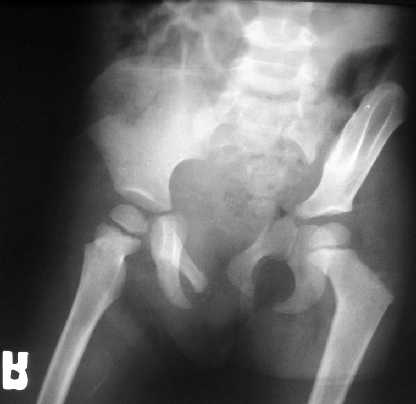

A 3 y-old girl, injured by after a traffic accident, no other skeletal and organ injuries. She was in skeletal traction now and initial, after skeletal traction AP views and CT scans of the pelvis were attached.